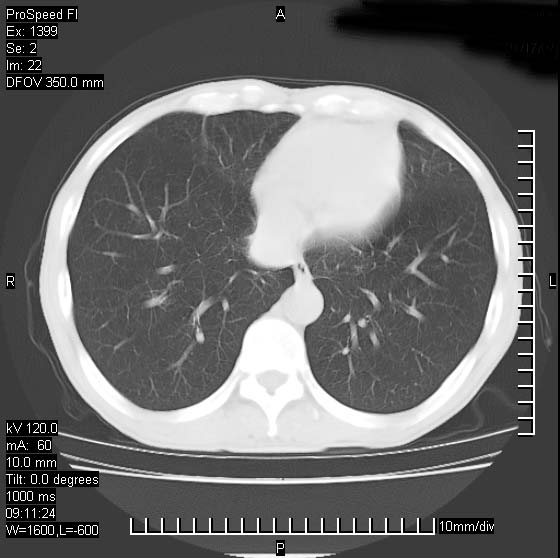

以下是引用卜一在2007-1-19 9:55:00的发言:[br]左肺沿胸膜下巨大肿块影,边缘呈分叶征,纵隔内见肿大淋巴结,右肺内另见一不规则结节影 .考虑:左肺周围性肺癌伴纵隔 右肺内转移.

以下是引用rgsyyf在2007-1-19 11:05:00的发言:[br]左肺上叶见形态不规则巨大软组织肿块影,边缘呈分叶征,纵隔内隆突下见肿大淋巴结,右肺内另见一不规则结节影 .考虑:左肺周围性肺癌伴纵隔即右肺内转移.